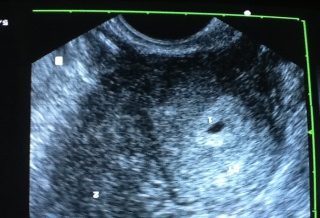

雙子宮雙胞胎 :

博元婦產科

試管嬰兒罕見案例